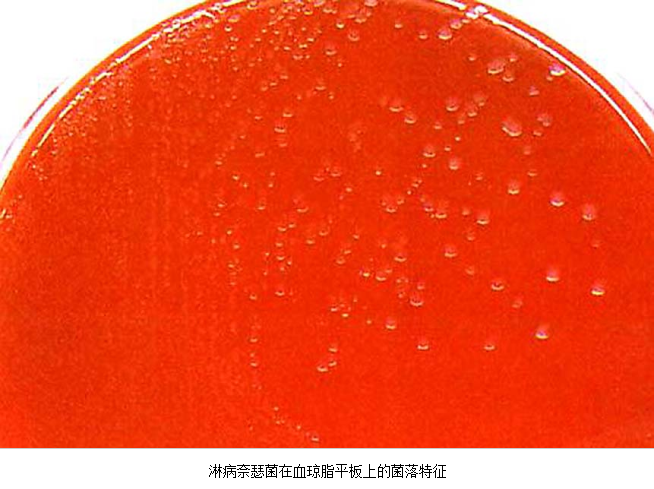

3.病原体检测 应作衣原体及淋病奈瑟菌的检测,以及有无细菌性阴道病及滴虫阴道炎。检测淋病奈瑟菌常用的方法有:①分泌物涂片革兰染色,查找中性粒细胞内有无革兰阴性双球菌,由于子宫颈分泌物的敏感性、特异性差,不推荐用于女性淋病的诊断方法。②淋病奈瑟菌培养,为诊断淋病的金标准方法。③核酸检测,包括核酸杂交及核酸扩增,尤其核酸扩增方法诊断淋病奈瑟菌感染的敏感性及特异性高。检测沙眼衣原体常用的方法有:①衣原体培养,因其方法复杂,临床少用。②酶联免疫吸附试验检测沙眼衣原体抗原,为临床常用的方法。③核酸检测,包括核酸杂交及核酸扩增,尤以后者为检测衣原体感染敏感、特异的方法。但应做好质量控制,避免污染。